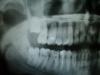

Кирил Рогожкин Опубликовано 24 июня, 2008 Автор Поделиться Опубликовано 24 июня, 2008 Снимок!!!! Проблемный зуб 2.6 и два рядом с ним. По поводу 3 и 4 врача - СПАСИБО По правде говоря эти два врач и так для меня авторитеты - вот только проблема: не сошлись во мнении!! Кстати по поводу приколов - версия с удалением меня не интересует Ссылка на комментарий

Кирил Рогожкин Опубликовано 25 июня, 2008 Автор Поделиться Опубликовано 25 июня, 2008 Вот снимок который сделали в поликлинике Ссылка на комментарий

Палыч Опубликовано 25 июня, 2008 Поделиться Опубликовано 25 июня, 2008 Вот снимок который сделали в поликлинике Качество снимка оставляет желать лучшего. Но и так можно диагносцировать:1 -зуб ранее лечен РФ методом;2 - в обл. медиального корня околоверхушечный воспалительный процесс;3 - воспаление в межзубном между 26 и 27. Лечени: 1 - чистка, кюретаж; 2 - повторная эндодонтия 26, 3 - лоскутная, на усмотрение доктора. Ссылка на комментарий

константин Опубликовано 25 июня, 2008 Поделиться Опубликовано 25 июня, 2008 на прицельном не очень четко все видно, но если судить оптг, то предпологается что резорбция костной ткани в обл. все 3-х корней данного зуба,рентгенологически прилегает к коням 7-гозуба, зуб ранее лечен, пломба в обл. проекции устья каналов, предпологает что, методом РФ. степень разрушения коронковой части более 50%. лечение данног зуба может оказаться неэффективно. можно преложить вариант: удаление 6-го зуба, далее имплантация и протезирование, или удаление, путем ортодонтического лечения мезиализация 7-го зуба, и постановка в зубную дугу 8-го зуба. но это сугубо мое личное мнение, основываясь на оптг.... Ссылка на комментарий

Гость Vini Vidi Vici Опубликовано 25 июня, 2008 Поделиться Опубликовано 25 июня, 2008 (изменено) Я вижу 2.6 ( резорциненный) с картиной хронического периодонтита у медиального корня, кариесы контактных поверхностей (смежных с 2.6) 2.7 и 2.5. Резорбция между 2.6 и 2.7 обусловлена хронической травмой пищевым комком. Перелечите 2.6( каналы)и вылечите кариес на контактных поверхностях. Пародонтологическое лечение приветствуется. Изменено 25 июня, 2008 пользователем Vini Vidi Vici Ссылка на комментарий

Dr. Stom Опубликовано 25 июня, 2008 Поделиться Опубликовано 25 июня, 2008 Качество снимка оставляет желать лучшего. Но и так можно диагносцировать:1 -зуб ранее лечен РФ методом;2 - в обл. медиального корня околоверхушечный воспалительный процесс;3 - воспаление в межзубном между 26 и 27. Лечени: 1 - чистка, кюретаж; 2 - повторная эндодонтия 26, 3 - лоскутная, на усмотрение доктора.послушайте Палыча. перелечите 26 и проверьте на жизнеспособность пульпы рядом стоящие зубы, хотя почти уверен что все проблемы в РФ 6 Ссылка на комментарий